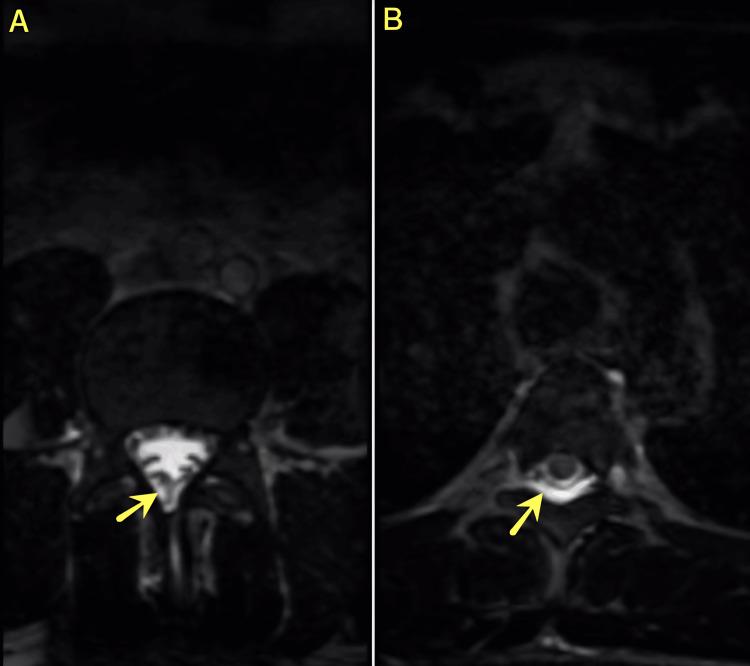

Pneumocephalus is an uncommon yet significant complication that can arise after lumbar discectomy and requires rapid diagnosis and intervention. Although cerebrospinal fluid (CSF) leakage is not frequently observed during these procedures, it can result from small, often inconspicuous dural defects that may be missed during surgery. This scenario underscores the importance of careful intraoperative inspection and vigilant postoperative monitoring to ensure timely recognition and management, thereby mitigating potential adverse outcomes. A 36-year-old male patient underwent an L5-S1 lumbar discectomy for disc herniation. Eight days postoperatively, he developed severe headache, neck pain, and nausea, accompanied by CSF leakage confirmed through beta-2 transferrin testing. Computed tomography revealed significant pneumocephalus, while high-resolution MRI demonstrated a subtle dural defect. Despite no macroscopically visible dural tear during re-exploration, applying an epidural blood patch successfully resolved both the CSF leak and pneumocephalus. This case underscores the value of advanced imaging, specifically high-resolution MRI, in identifying subtle dural defects that may not be apparent during surgery. Detecting the minor CSF leakage was essential for directing subsequent management and avoiding further complications. Early recognition of postoperative symptoms combined with comprehensive imaging assessment is crucial in the management of post-discectomy pneumocephalus. The rapid resolution observed after applying an epidural blood patch supports its role as a primary intervention strategy, even in cases where dural tears are not macroscopically evident.

气颅是腰椎间盘切除术后可能出现的一种罕见但严重的并发症,需要快速诊断和干预。虽然在这些手术过程中脑脊液(CSF)漏并不常见,但它可能源于手术中可能被遗漏的小的、通常不明显的硬脊膜缺损。这种情况凸显了术中仔细检查和术后密切监测的重要性,以确保及时识别和处理,从而减轻潜在的不良后果。一名36岁男性患者因椎间盘突出症接受了L5-S1腰椎间盘切除术。术后8天,他出现严重头痛、颈部疼痛和恶心,经β-2转铁蛋白检测证实伴有脑脊液漏。计算机断层扫描显示有明显的气颅,而高分辨率磁共振成像显示有一个细微的硬脊膜缺损。尽管再次探查时没有肉眼可见的硬脊膜撕裂,但应用硬膜外血贴成功解决了脑脊液漏和气颅问题。该病例强调了先进成像技术,特别是高分辨率磁共振成像,在识别手术中可能不明显的细微硬脊膜缺损方面的价值。检测到轻微的脑脊液漏对于指导后续治疗和避免进一步并发症至关重要。术后症状的早期识别与全面的影像评估相结合,对于椎间盘切除术后气颅的管理至关重要。应用硬膜外血贴后观察到的快速缓解支持了其作为主要干预策略的作用,即使在硬脊膜撕裂肉眼不可见的情况下也是如此。